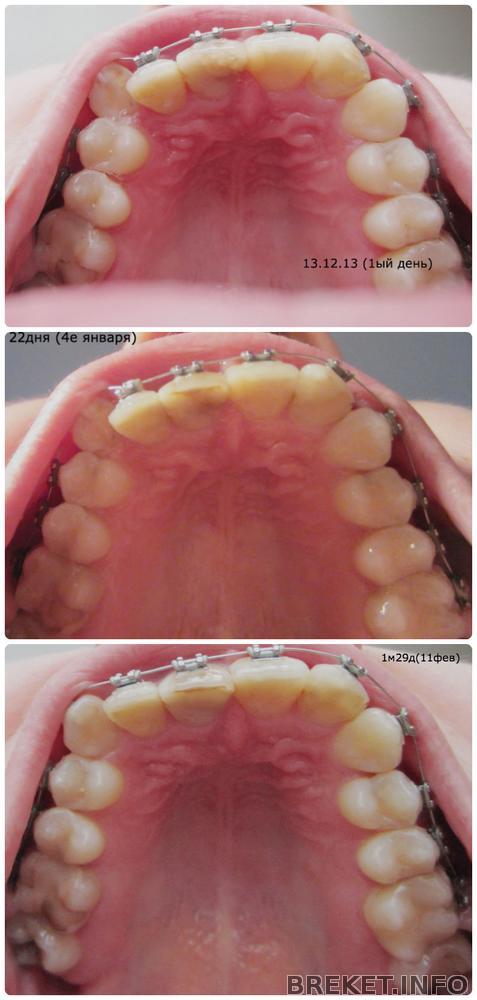

2 месяца (ну почти)

Пока есть время,решила сделать коллажики, до юбилейчика в 2 месяца еще 2 дня, но возможность есть только сейчас.

Наконец-то я вижу изменения!

Этих подвижек я ждала так долго, особенно первые недели психовала

,каждый день заглядывала в рот,пытаясь что-то заметить. Но активно зубки начали двигаться неделю назад где-то.

Конечно, самое радостное для меня-это клык, который после смены лигатур активно распихивает своих соседей, занимая свое законное место. То то я теперь каждое утро не могу дотронуться до единицы со стороны этого бойкого, да и весь ряд справа ноет переодически.. Поймала себя на мысли, что мне нравится эта боль ![]()

Вот моя пасть, и как же радостно в нее теперь смотреть ![]()

Отлично видно, как клык протискивается, да и зубы в рядах справа и слева встают друг напротив друга!!

Может у меня глюки и я придумываю,но похоже, что челюсть стала расширяться! А?

За это же говорит появление нехилой такой дистальной щели! теперь мой прикус не только глубокий,но и дистальный,блин((